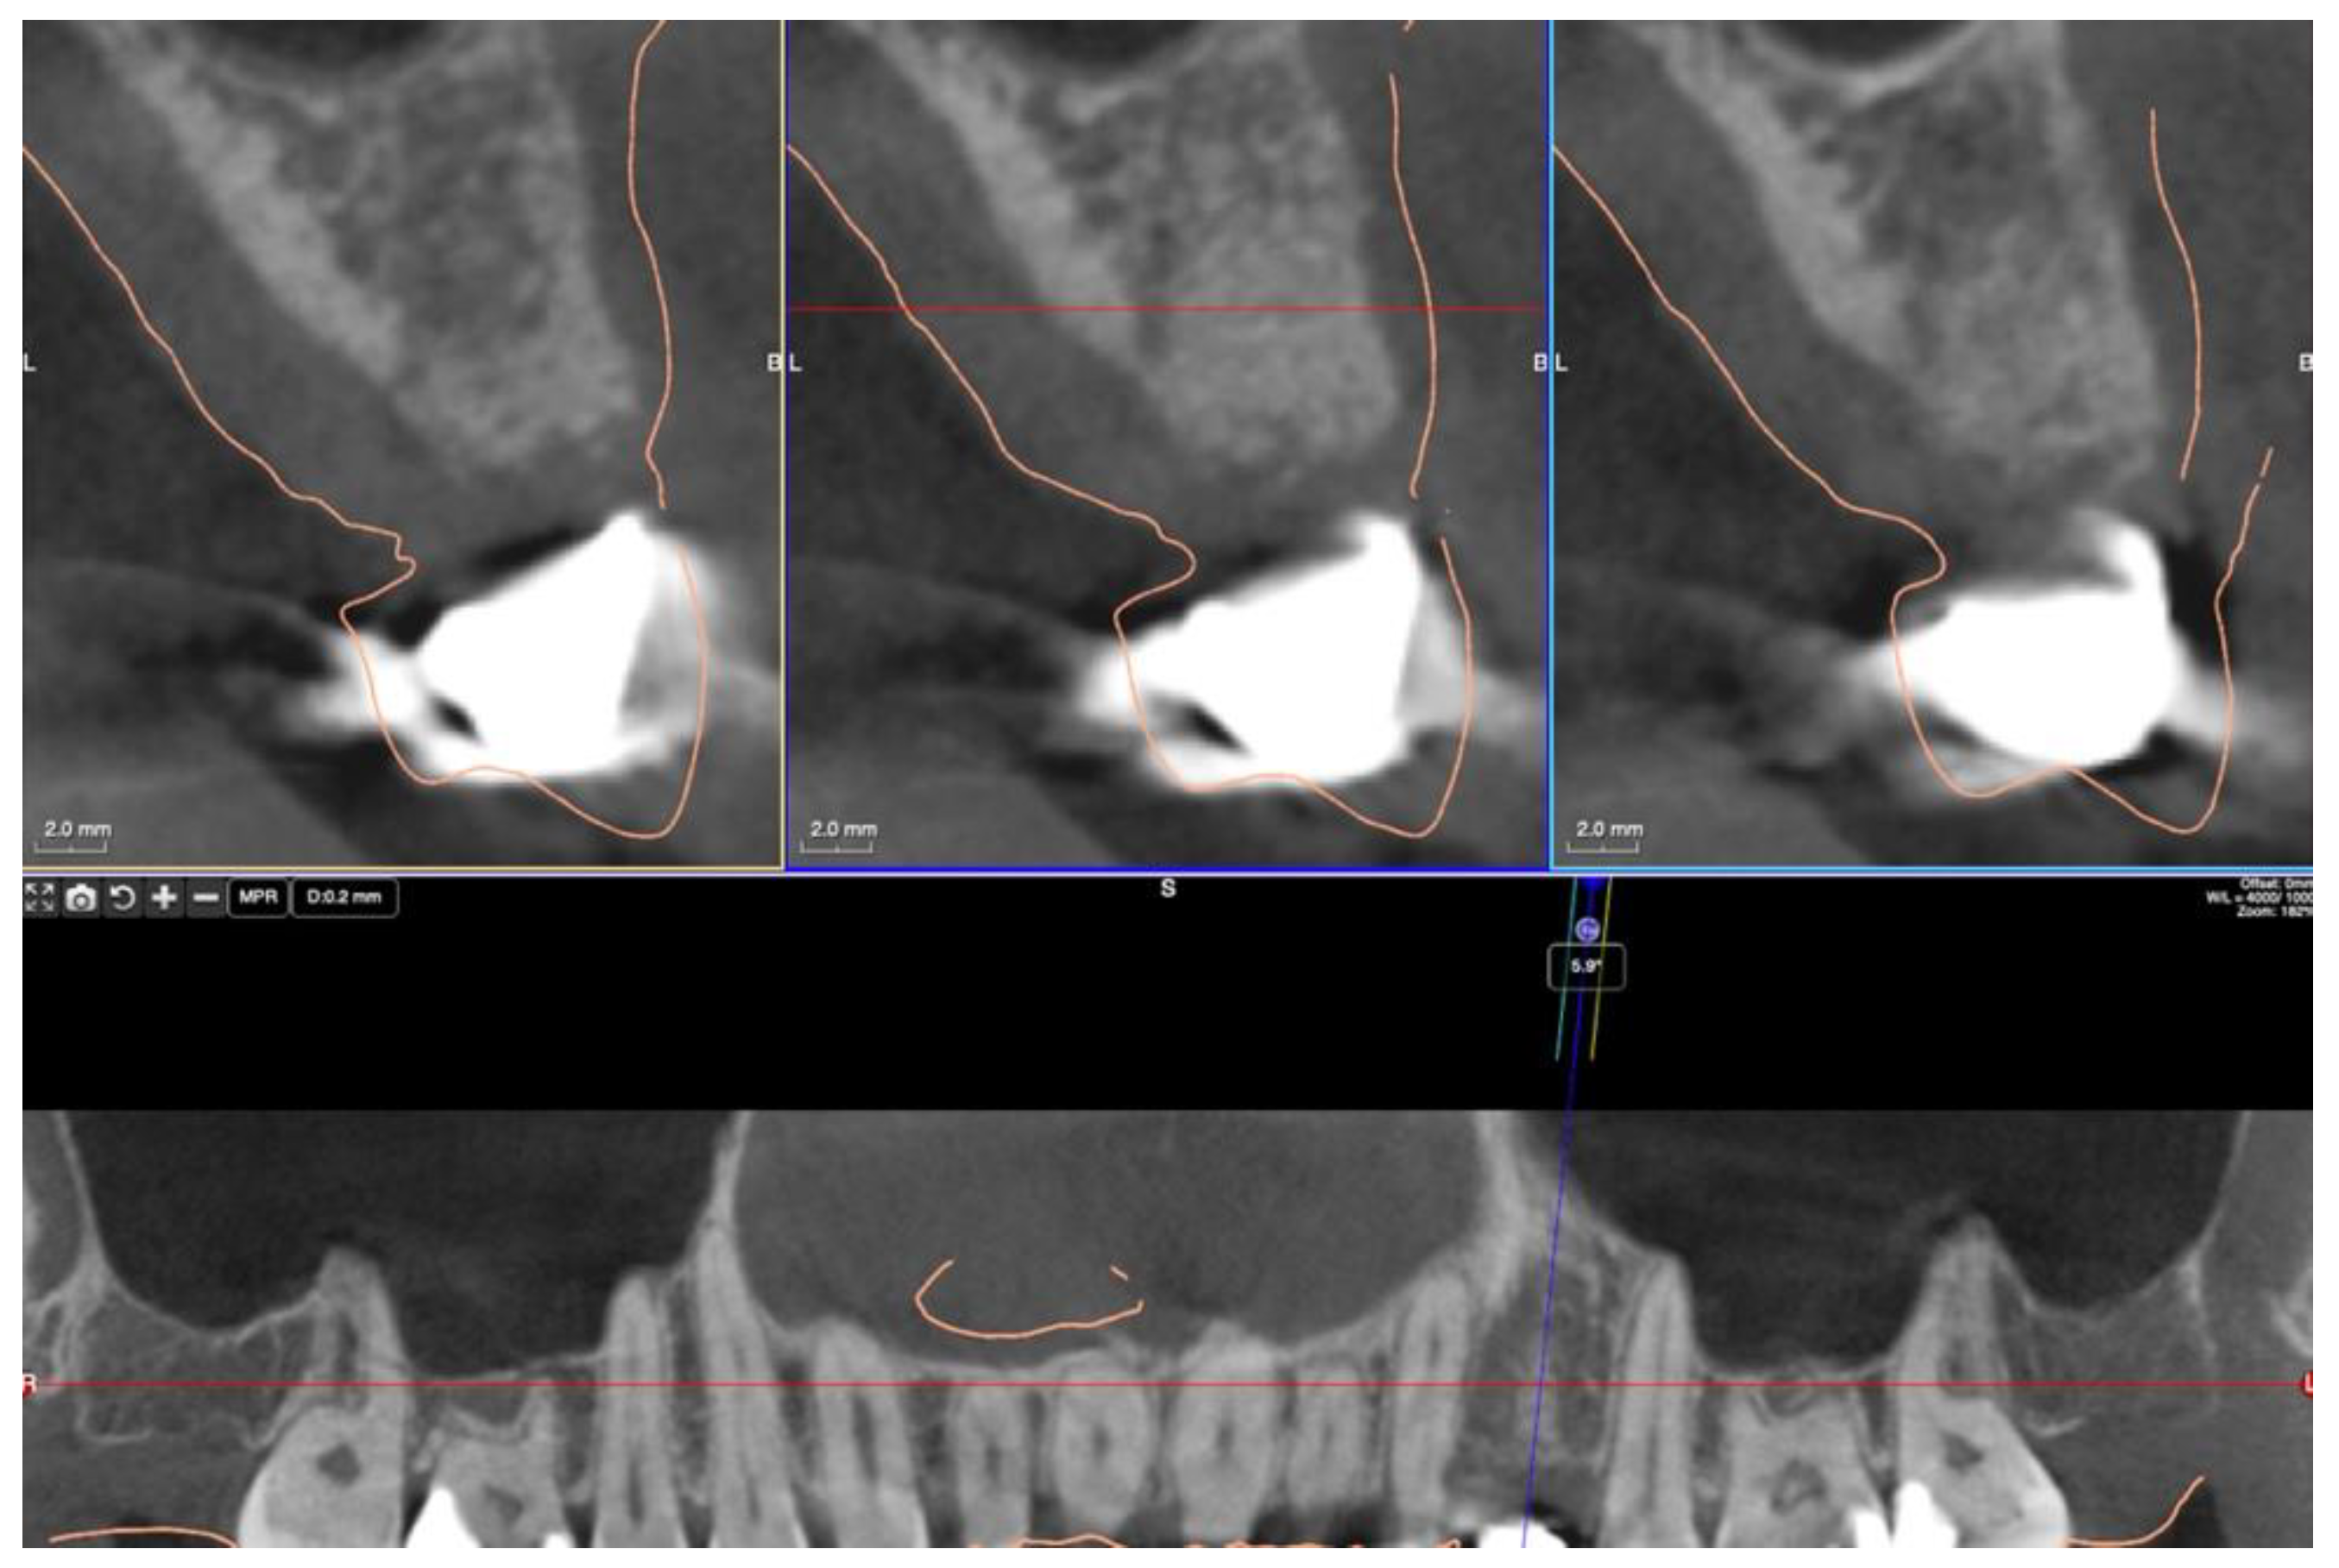

3.2. Ridge Dimension